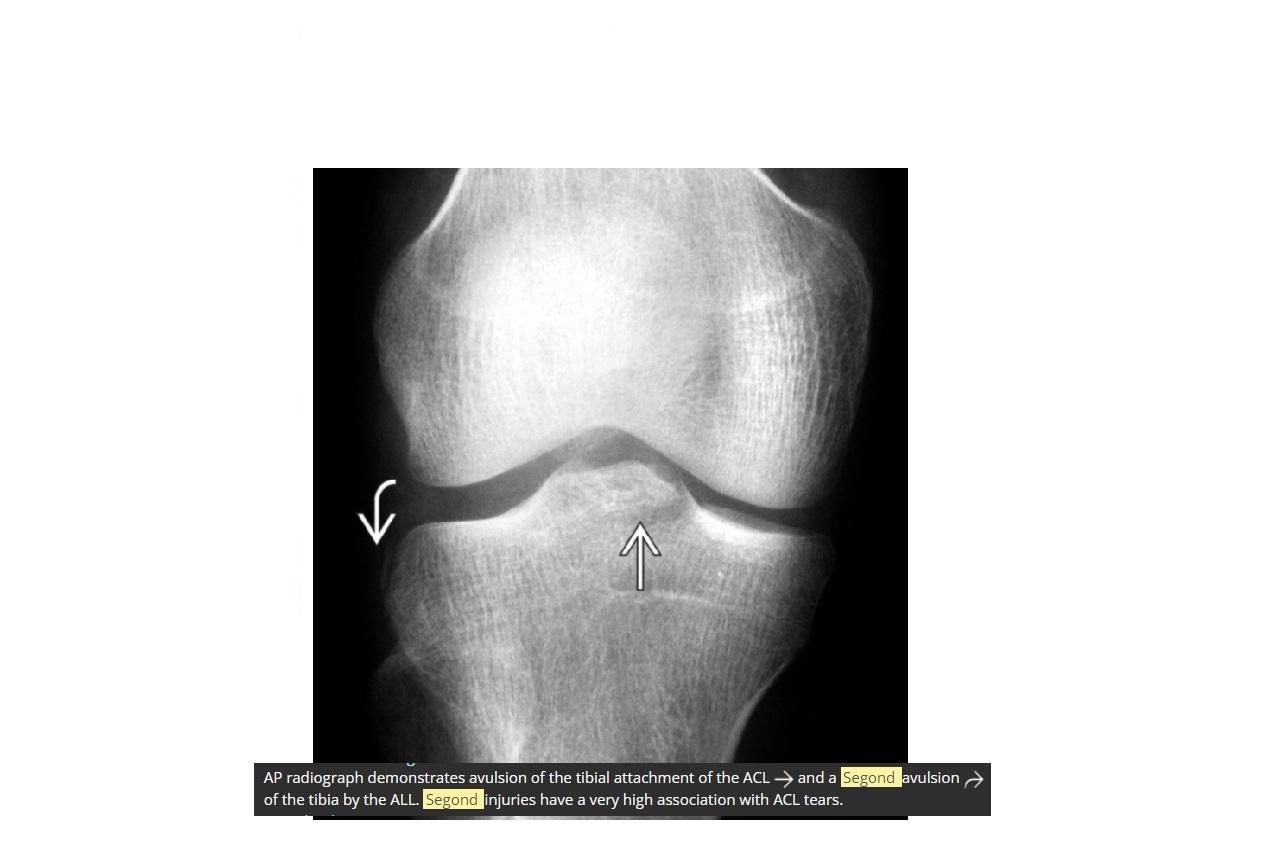

Segond fracture?

Lateral tibial plateau

Associated with ACL tear (75%) and internal rotation

Reverse Segond fracture?

Medial tibial plateau

Associated with PCL tear with external rotation. Associated with medial meniscus injury.